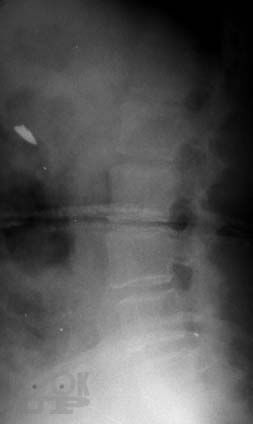

Практическое руководство «Рентгенодиагностика позвоночника для мануальных терапевтов» обобщает многолетний опыт сотрудничества автора – рентгенолога с мануальными терапевтами и освещает проблемы лучевой диагностики с точки зрения мануальной терапии. В руководстве представлен метод системного анализа рентгенограмм позвоночника. Особое внимание уделено клиническим аспектам применения данного метода в практике мануальной терапии: отражены методики экспресс-диагностики пространственного положения структур краниовертебральной зоны, позвоночника и крестца, описаны способы распознания, регистрации, хранения и передачи данных об индивидуальных характеристиках позвоночника каждого больного. Приведены классификации, рентгенологические проявления и особенности диагностики аномалий развития позвоночника в практике мануальной терапии. Показаны возможности и перспективы метода системного анализа рентгенограмм позвоночника для совершенствования лучевой диагностики в мануальной терапии и в восстановительной медицине. Руководство содержит большое количество рентгенограмм, схем, рисунков и таблиц.